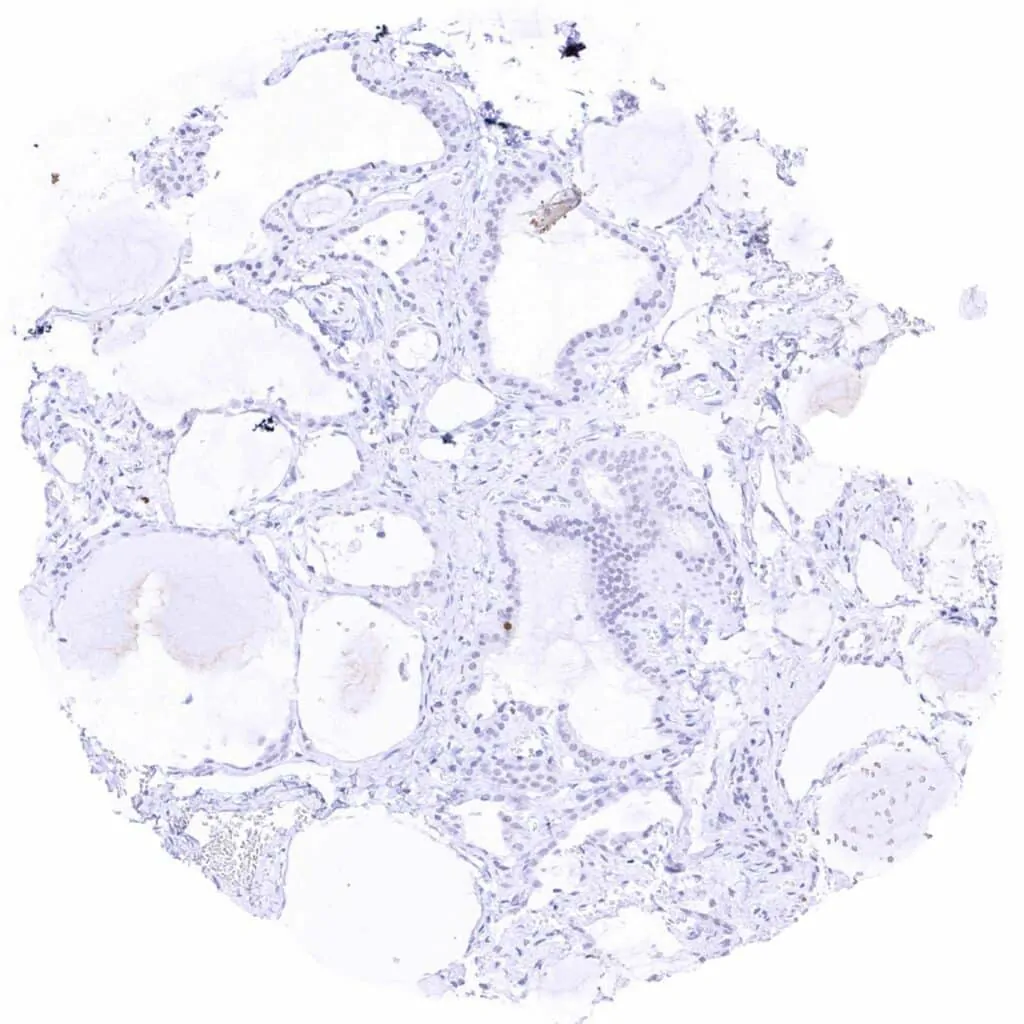

Thyroid gland